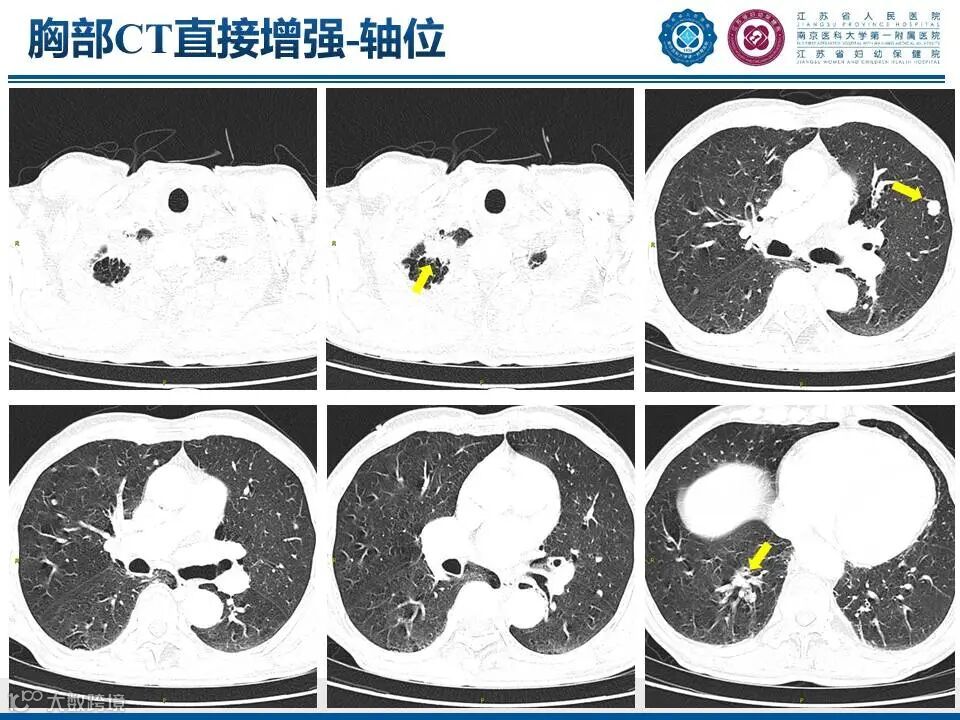

肺上沟瘤

——肩痛背后的致命危机